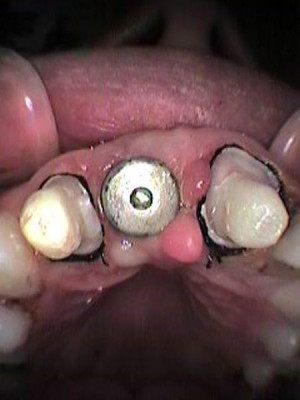

Vista oclusal inicial

Cuatro meses después se coloca tornillo de cicatrización

Se coloca poste de impresión